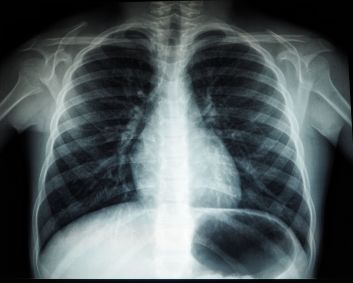

A tuberculose é uma doença infecciosa, transmitida por uma bactéria, que atinge especialmente os pulmões.

De acordo com ele, é “relativamente fácil” fazer o diagnóstico, com um teste de escarro, disponível no SUS, e raio-x de pulmão.